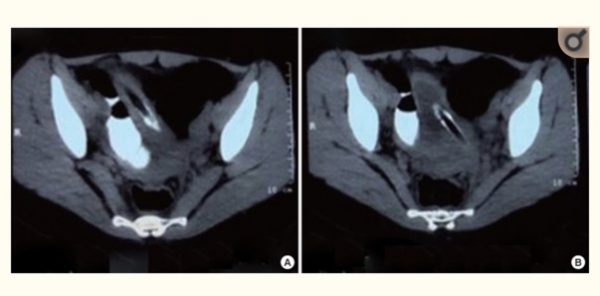

「Rare foreign body in bladder」(Medicine (Baltimore) . 2018 Apr; 97 (17) : e0519.)というタイトルの医学論文で2018年に発表されています(おお!私の最近のトレンドだよ説は正しいかも)。

この症例に使用された異物は67個の直径5㎜の「magnetic balls」なので、お風呂の栓に付いているチェーンでは無いかも、残念。

しかし、「67 magnetic steel balls」って本来の使用方法は何なんだろうね。ちなみにこの症例は中国のものです。